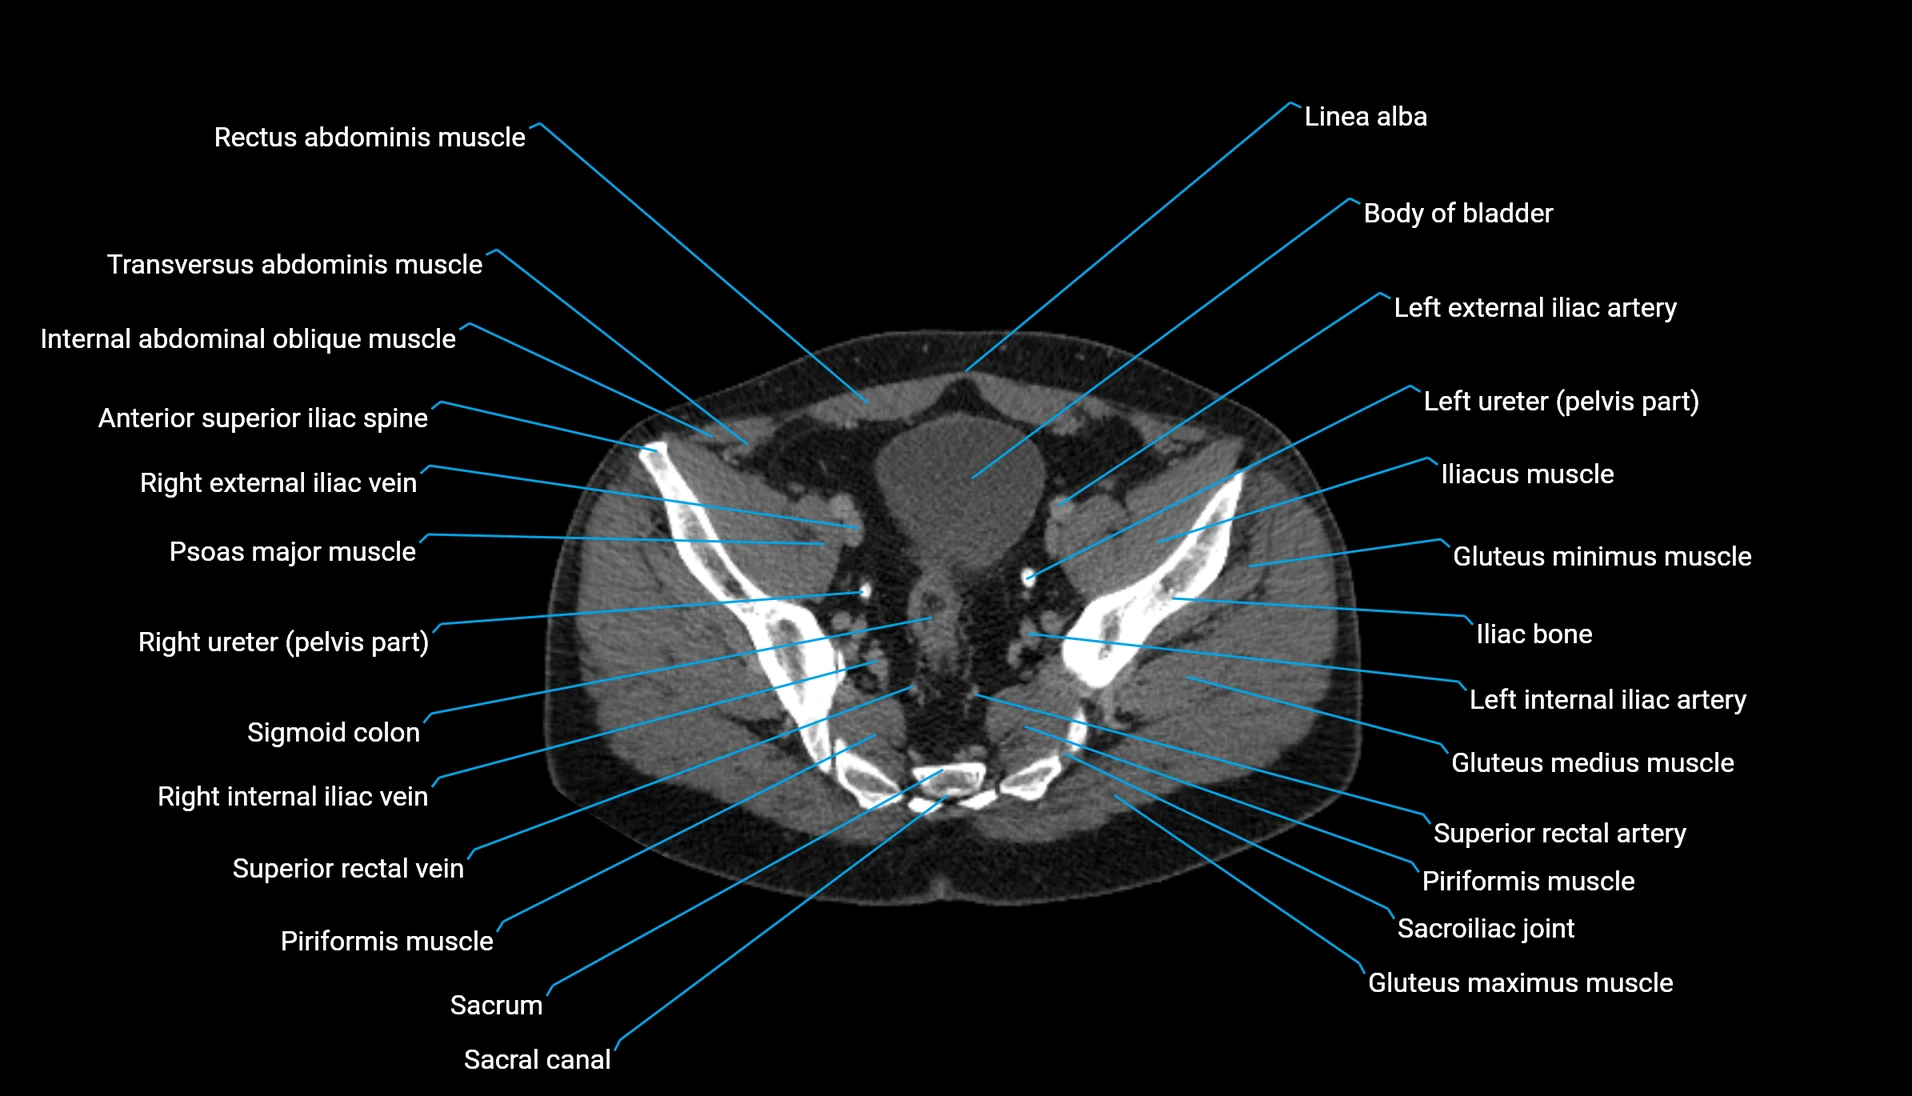

CT Appearance

Non-contrast CT:

-

Demonstrates cortical bone of acetabular rim in excellent detail

Detects fractures, dysplasia, retroversion, or bony overcoverage (pincer impingement)

3D reconstructions used in preoperative hip surgery planning

CT VRT 3D image

CT image